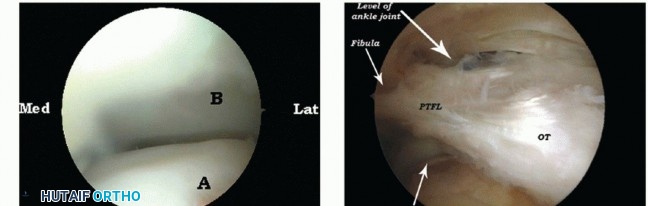

After removal of the thin joint capsule, the posterior subtalar joint can be inspected (TECH FIG 3A).

At the level of the ankle joint, the posterior tibiofibular and talofibular ligaments are identified and the posterior ankle joint can be visualized (TECH FIG 3B).

- TECH FIG 3 • A. Arthroscopic views of the posterior compartment of the subtalar joint showing the calcaneus

(A) and the talus (B). B. Endoscopic overview of the posterolateral aspect of the ankle joint. Os trigonum (OT) and its connection to the posterior talofibular ligament (PTFL). C. Application of the soft tissue distractor.